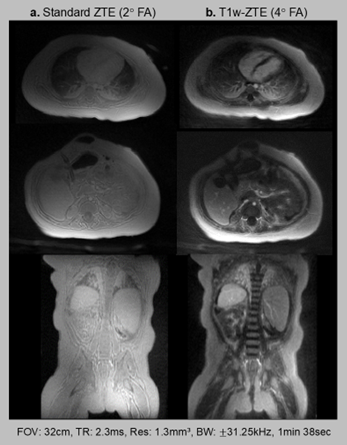

Loud acoustic noise is well-acknowledged as one of the main reasons for patient discomfort in MRI, especially for pediatric patients. For unsedated neonates scanned with the feed-and-swaddle technique, the loud acoustic noise can often wake them up and lead to an unsuccessful exam. Zero echo time (ZTE) imaging (based on RUFIS) enables the unique combination of low acoustic noise and high sampling efficiency, where >99% of each TR can be used for sampling. Our research develops upon standard ZTE to enable (i) quiet T1-weighted imaging and (ii) quiet, dynamic imaging with flexible temporal resolution. We jointly design the quiet acquisition along with an inverse problem-based reconstruction to enable novel applications of quiet MRI in clinical settings.

- Quiet T1-weighted Imaging: Developed novel acquisition and reconstruction methods to enable T1-weighted imaging with minimal acoustic noise using Zero Echo Time (ZTE) sequences